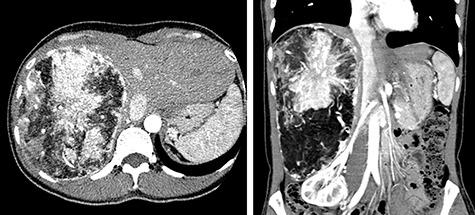

A 45-year-old woman was referred to our hospital with a huge liver tumor that had been diagnosed as a hepatic angiomyolipoma (HAML) 5 years previously. At the time of referral, it had enlarged from 12 to 20 cm within the previous 5 years and become symptomatic. Enhanced computed tomography revealed a very large, well-defined, low-density mass occupying the entire right lobe of the liver. The patient underwent right hemi-hepatectomy. The resected specimen weighed 1620 g and measured 20 × 14 × 8 cm. The pathological diagnosis was confirmed as benign HAML. The estimated growth rate of this tumor was 44% per year with a doubling time of 826 days. Although the majority of HAMLs are stable lesions, resection should perhaps be considered when the tumor is known to be growing and exceeds 6 cm in diameter, even if it has been diagnosed as benign.

一名45岁女性因巨大肝脏肿瘤被转诊至我院,该肿瘤5年前被诊断为肝脏血管平滑肌脂肪瘤(HAML)。转诊时,肿瘤在过去5年内从12厘米增大至20厘米并出现症状。增强计算机断层扫描显示一个非常大的、边界清晰的低密度肿块占据了整个肝右叶。患者接受了右半肝切除术。切除标本重1620克,尺寸为20×14×8厘米。病理诊断确诊为良性HAML。该肿瘤的估计生长速率为每年44%,倍增时间为826天。尽管大多数HAML是稳定病变,但当已知肿瘤在生长且直径超过6厘米时,即使已诊断为良性,也许仍应考虑进行切除。